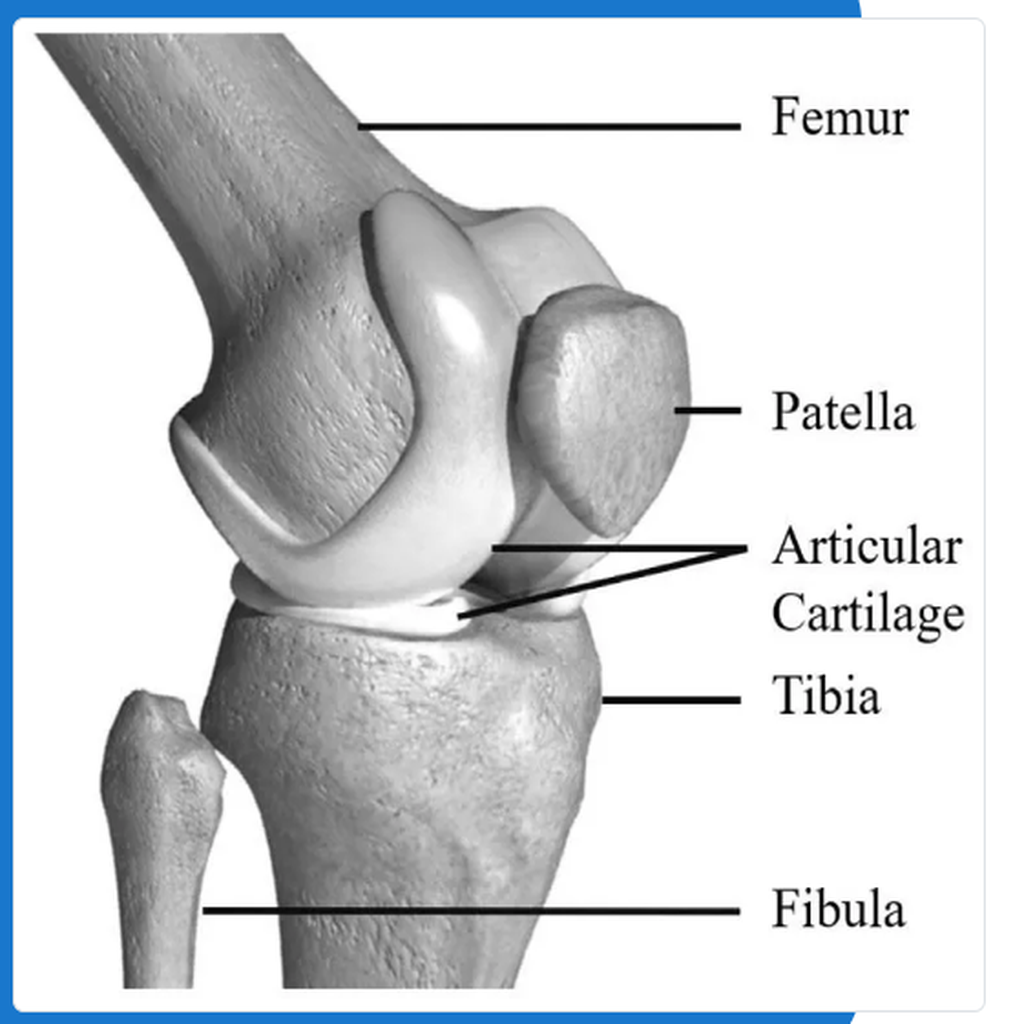

When it is healthy, the knee is a remarkable mechanism. In a healthy knee, a layer of cartilage covers the surface of the joint allowing smooth motion.

Total Knee Replacement is the surgical removal of the damaged joint and replacing it with an artificial joint that is attached to the thigh bone (femur) and the shinbone (tibia).

This is known as a prosthesis or an implant. In most cases, bone cement is used to fix the artificial joint to the thigh and shinbone.

We remove the damaged cartilage and bone from the knee to replace with metal and plastic molded implants. The new implants make the joint movements smooth enabling them to work freely and relieving you of the pain caused earlier.